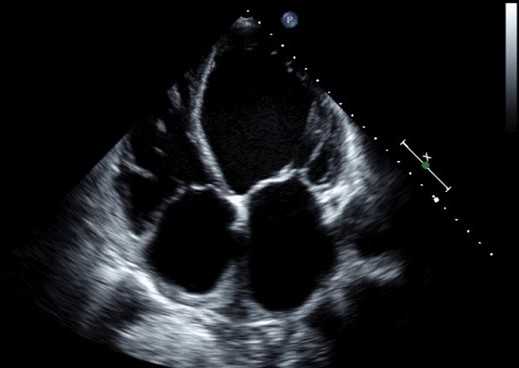

Дилатационная кардиомиопатия характеризуется значительным расширением полости левого желудочка (ЛЖ) и снижением глобальной систолической функции. Как конечный диастолический, так и конечный систолический размеры и объемы увеличиваются, а переменные систолической функции (фракции выброса, фракции укорочения, продольного систолического движения митрального кольца, ударного объема и сердечного выброса) равномерно уменьшаются. С постепенным расширением по короткой оси ЛЖ на эхокардиографии, полость ЛЖ становится более сферической, с индексом сферичности (измеренная длинная ось/короткая ось) приближается к значению 1 (обычно ≥1.5). Толщина стенок варьируется, но обычно в пределах нормы; однако, масса ЛЖ равномерно увеличивается. Сократимость, как правило, уменьшается по всем сегментам, но накладываются региональные аномалии движения стенок, которые могут также присутствовать. Подобные находки встречаются у пациентов с обширной ишемией миокарда, миокардитом, кардиомиопатиями, гепатитом, гемохроматозом, кардиомиопатия периспритом, саркоидоз, острым катехоламиновым кризисом, синдромом приобретенного иммунодефицита, тяжелого сепсиса или отравления доксорубицином (препараты адриамицин).

Дилатационная кардиомиопатия и ЭхоКГ. Это патологическое состояние характеризуется расширением камер сердца, особенно левого желудочка (ЛЖ), хотя часто вовлекаются все другие камеры, с уменьшенной толщиной стенки и уменьшенным движением стенки. Заболеваемость оценивается в 6,0 на 100 000 в год. Большинство случаев изолированы, хотя выявлены некоторые семейные формы. Снижение подвижности стенки ЛЖ обычно носит глобальный, а не региональный характер, как видно при систолическом нарушении ЛЖ из-за ишемической болезни сердца (ишемия или инфаркт).

M-режим и 2-D эхокардиография показывает:

- Расширение всех камер сердца (левого и правого желудочков и предсердий) - увеличение конечного систолического и конечно диастолического размера и объема ЛЖ

- Уменьшение толщины стенки и ее подвижности (от легкого до тяжелого) - снижение фракции выброса и частичного укорочения, уменьшение подвижности межжелудочковой перегородки и верхушки ЛЖ

- Внутрисердечный тромб (ЛЖ и ЛП).